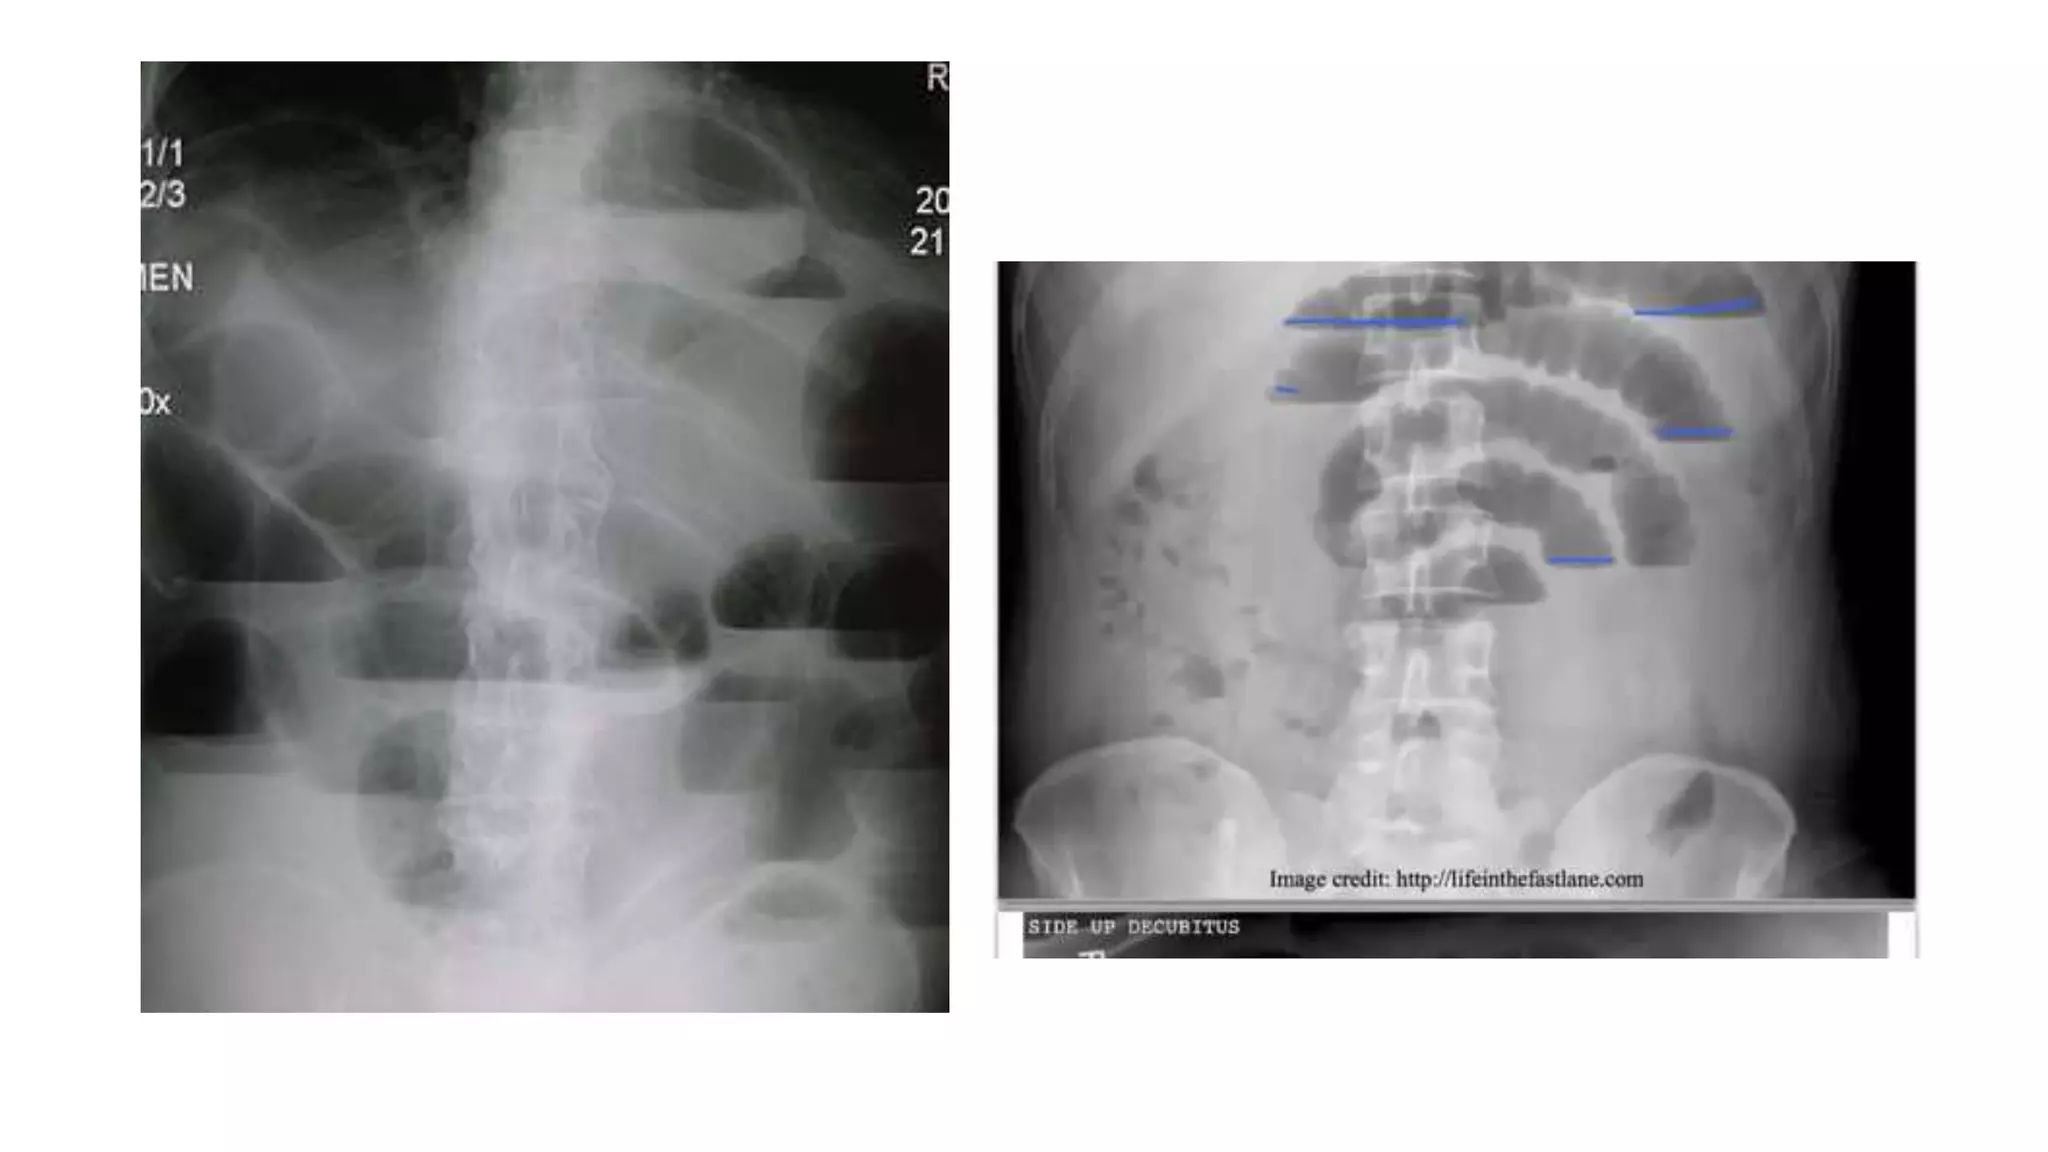

• The basic radiologic examination should include:

• If the patient cannot be placed into an upright position, a

lateral decubitus abdominal film can show free air and/or air-

fluid levels.

Radiological signs to look for:

• Dilation >3 cm: The small bowel is dilated if it measures over 3 cm in

diameter.

• Central location: The dilated loops are more likely to be centrally

located on the abdominal radiograph.

• Valvulae conniventes: These are the mucosal folds of the small

intestine. They are thin, closely spaced and classically seen as a

continuous thin line across the entire width of the bowel.

• Air fluid level in upright position